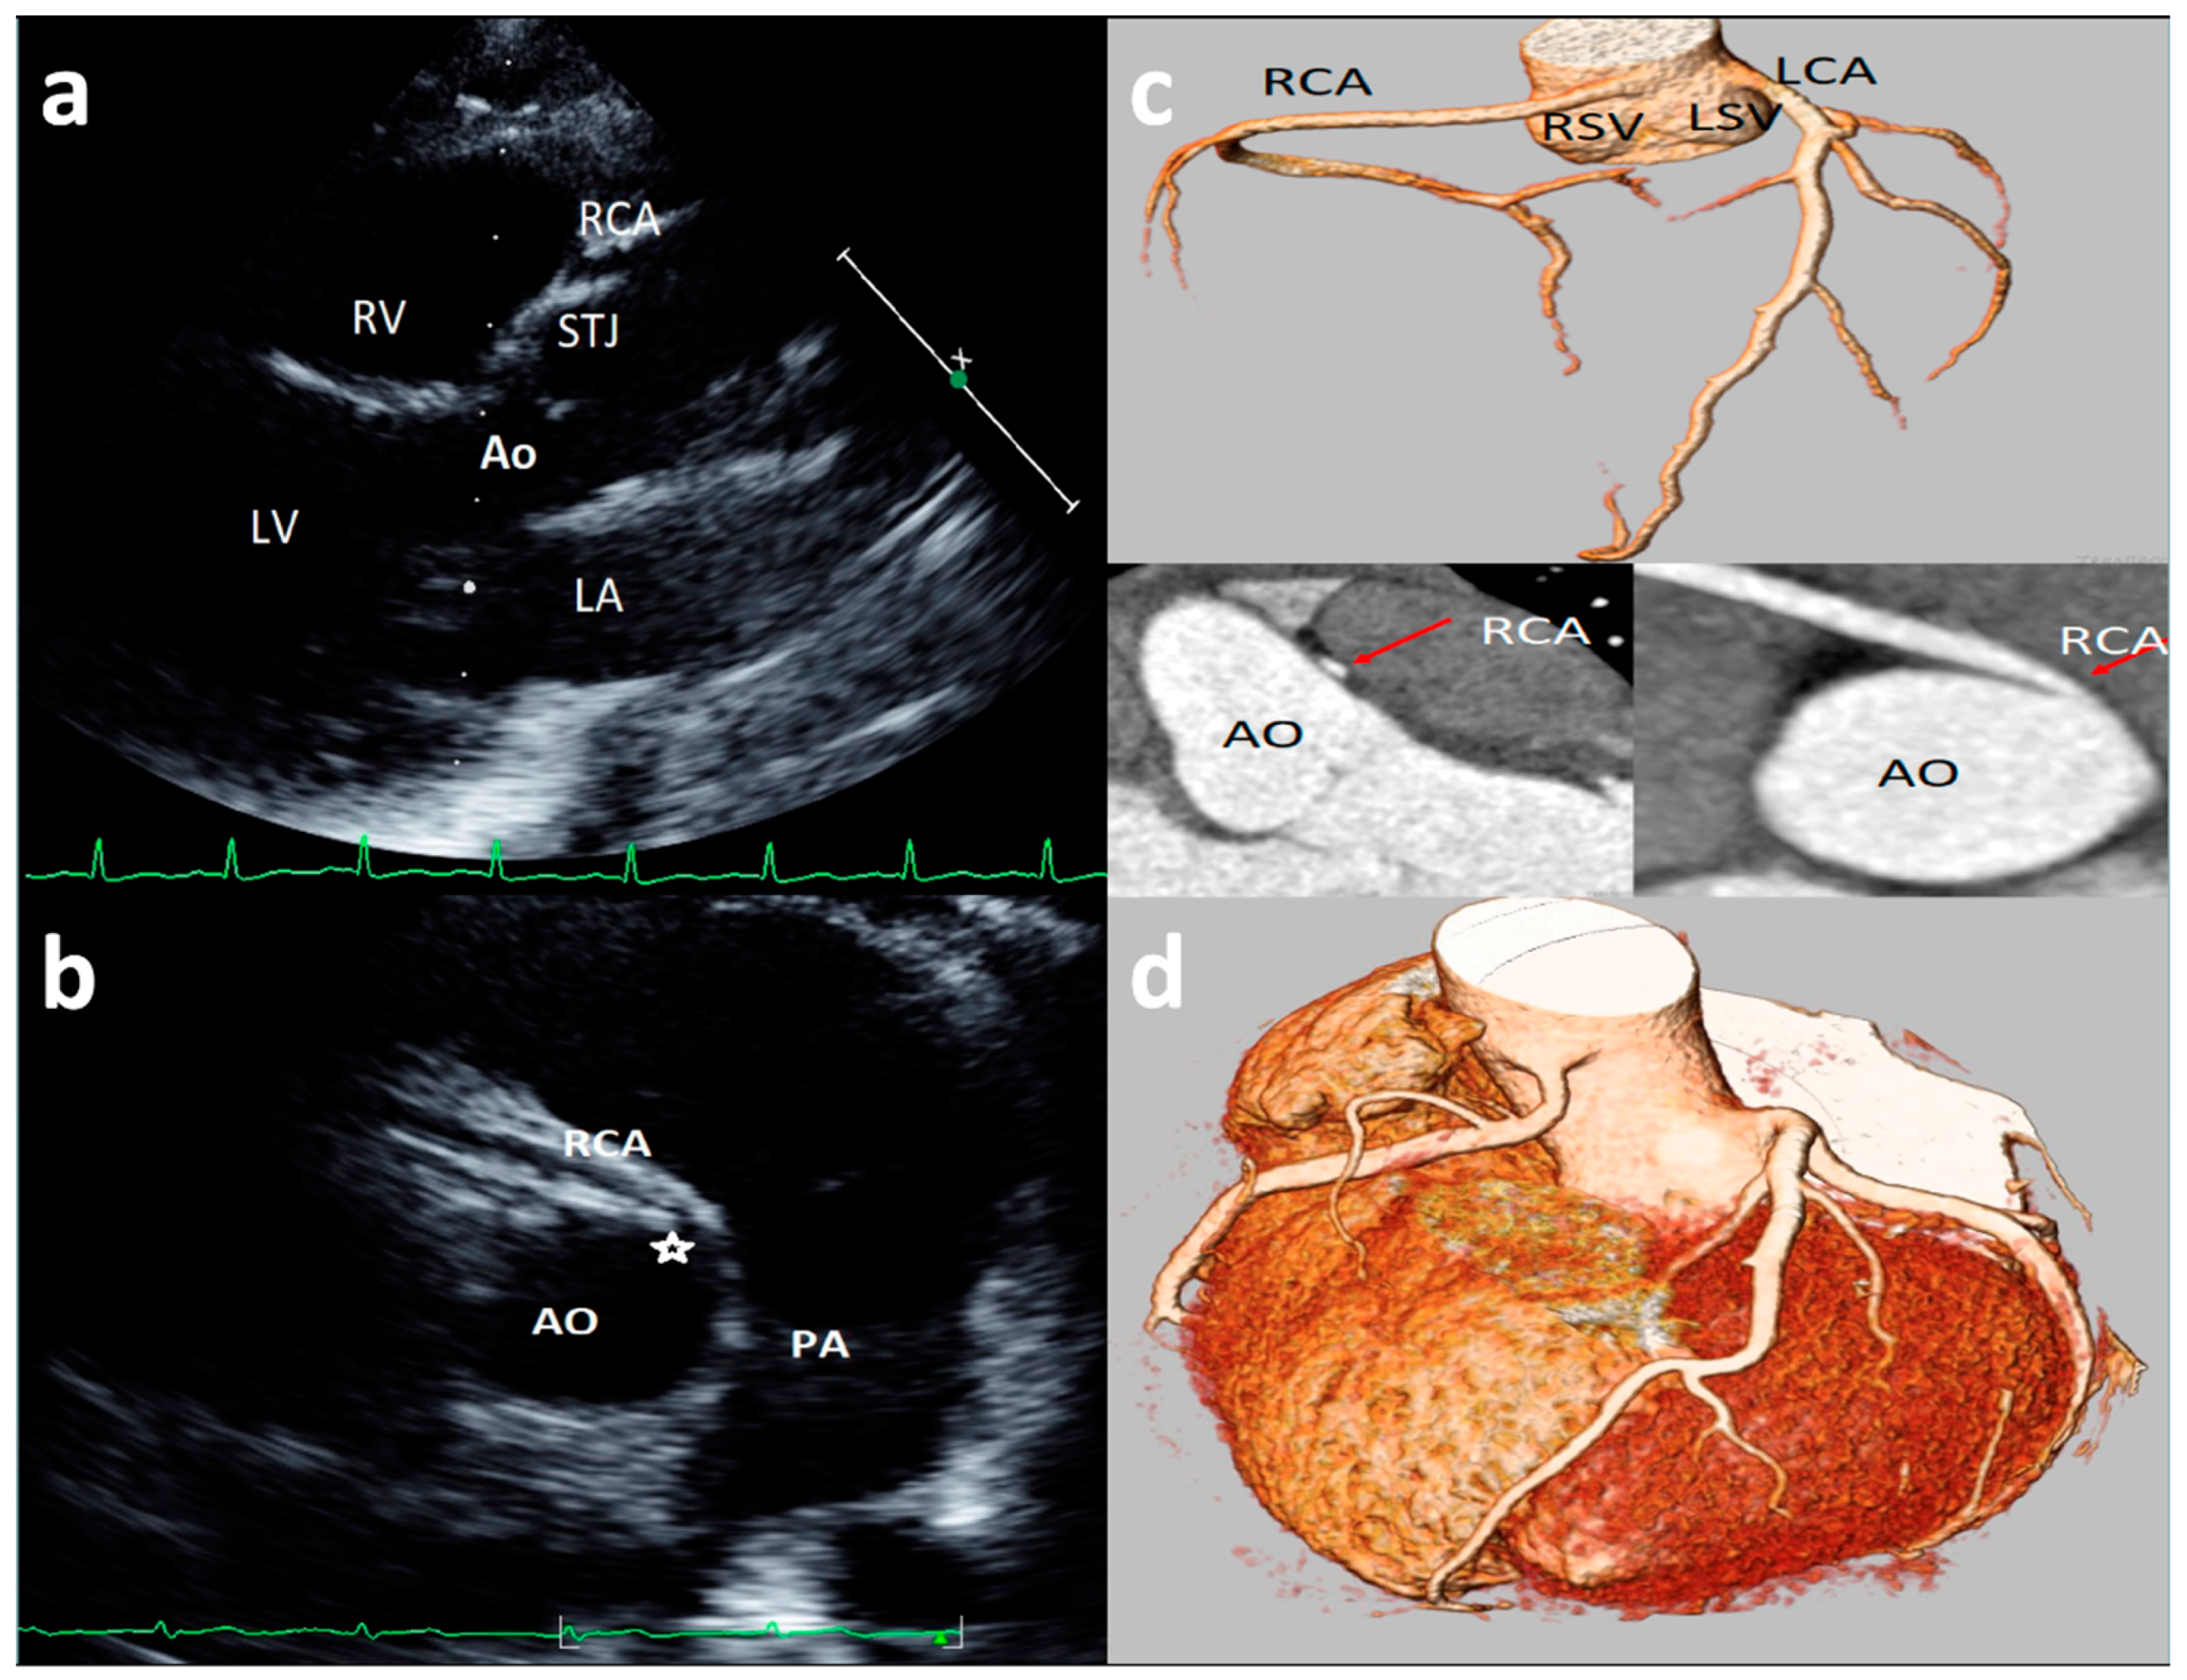

3.6. Coronary Artery High Take-Off

High take-off coronary artery is a rare anomaly [33,34,35,36,37,38,39,40,41,42,43] that may present in isolation or associated with other congenital cardiac malformations [35,36,37,38,39,40,41,42,43], mainly identified for the RCAs (up to 84.46% of cases) [33]. There is still limited literature on the visualization and definition of RCA high take-off by echocardiography [13,14,23]; although there is not a consensus on the definition of high take-off by echocardiography, all the studies included in the present review defined high take-off as an origin above or distal to the sinutubular junction (STJ) [13,14,23]. An example of high take-off of RCA from our case series is reported in Figure 3. A very recent [13] study, of 1045 consecutive elite adolescent football players, identified coronary high take-off origin in 13 subjects (i.e., 1.14%). Eccentric RCA origin with a high take-off and partial intra-arterial course was observed in two cases (with no slit-like ostium and no intramural course); high take-off origin of the RCA with acute angle was observed in one case; high take-off of the RCA origin (with no intramural or slit-like orifice) was observed in 11 cases. Of the latter 11 cases, diagnosis was feasible only from the parasternal long-axis view, where the ostium of the RCA was measured from 2.3 to 6.8 mm above the sinutubular junction [13]. Lytrivi et al. [24] documented RCA high take-off in 53 cases (0.36%), LCA high take-off in four cases, and high take-off of both the coronary arteries in two cases of a valuable cohort of 14,546 pediatric subjects [23].

Figure 3. Asymptomatic 17-year-old boy evaluated for the presence of two premature ventricular beats at peak of stress test in routine preparticipation evaluation for sports competition. Parasternal long-axis view showing right coronary artery (RCA) high take-off coronary artery above the sinus of Valsalva (a). The acute angulation origin is clearly visualized in short-axis view (b) and was confirmed at CT (c). After CT confirmation of the defect, a myocardial scintigraphy was performed revealing a small ischemia (8%) in the RCA territory at peak. We advised sport restriction. Ao = aorta, LCA = left common coronary artery, RCA = right coronary artery, LSV = left sinus of Valsalva, RSV = right sinus of Valsalva. (d) is an example of 73-year-old man showing symptoms of dyspnea. 3D-Volume Rendering CCTA showing the right dominant coronary artery (RCA) high take-off two centimeters distal to the sinutubular junction at the level of the anterior ascending aortic wall.